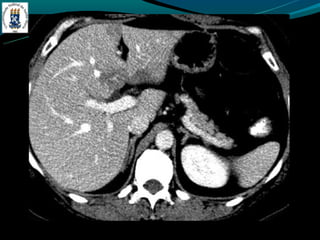

Peliose hepática